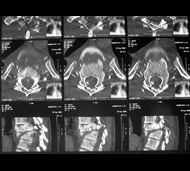

- Комп'ютерну томографію (КТ). КТ може надати краще зображення патології, видимої на рентгенівських знімках. Цей вид обстеження використовує комп'ютер, щоб відтворити серію зображень поперечного перерізу, які можуть виявити проблеми, пов'язані з кістками, дисками і інші.